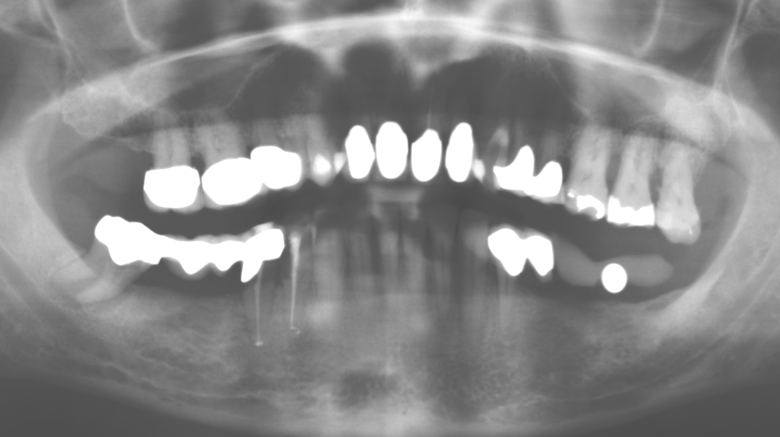

The ten-year check-up revealed no indications of advancing clinical attachment loss or peri-implant bone substance loss (Fig. 3).

Fig. 3: Panoramic radiograph after ten years with implants.